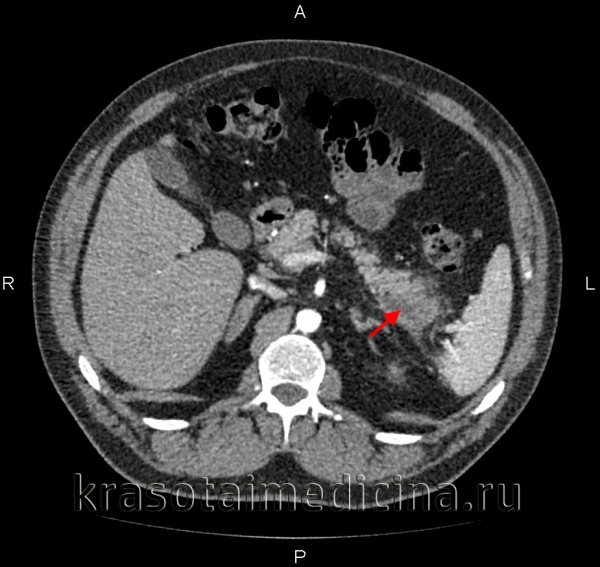

КТ органов брюшной полости. Панкреатит (в области хвоста поджелудочной железы) с наличием отека ее паренхимы, жидкостного содержимого вблизи ее края, на фоне утолщение фасции Героты слева

КТ ОБП. Панкреонекроз. Диффузный отек и нарушение структуры поджелудочной железы, отсутствие накопления контраста в ее паренхиме.